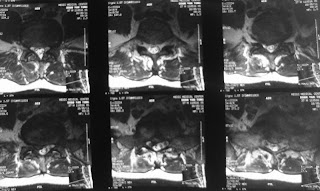

24-5-2011 l5-s1,l4-5lss